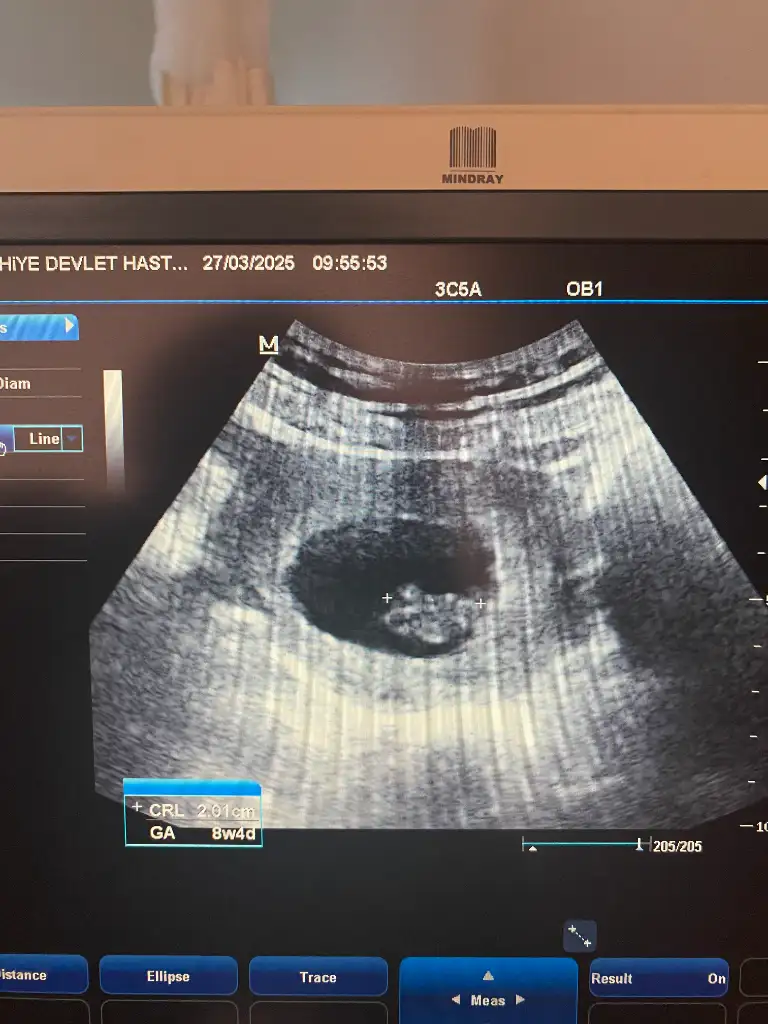

Hadi yaa 1 hafta deha beklicem o zamanBen 8+4te gördüğümde böyle bir bebek görüntüsü yoktu canım ama karın ultrasonuydu, vajinalde belki daha net seçilebilir başı vs

Canım burda 8+4 tam bir bebek görüntüsü yok merak ettiğin için atayım dedim yarın böyle bişeyle karşılaşabilirsin ama tabi her bebeğin gelişimi farklıYaa çok tebrik ederim çok güzelbi sey sorcam ben yarın 8+4 olcam ve kontrole gitcem. Bu şekilde görür müyüm acaba sen 8 haftalikken de gitmiş miydin

8 haftalıkken daha minicikti canım atayımYaa çok tebrik ederim çok güzelbi sey sorcam ben yarın 8+4 olcam ve kontrole gitcem. Bu şekilde görür müyüm acaba sen 8 haftalikken de gitmiş miydin

Ben evham yapıp sık kontrole gidenlerdenim mesela son kontrolüm üzerinden daha 6 gün geçtiCanım burda 8+4 tam bir bebek görüntüsü yok merak ettiğin için atayım dedim yarın böyle bişeyle karşılaşabilirsin ama tabi her bebeğin gelişimi farklı

Yaaa8 haftalıkken daha minicikti canım atayım